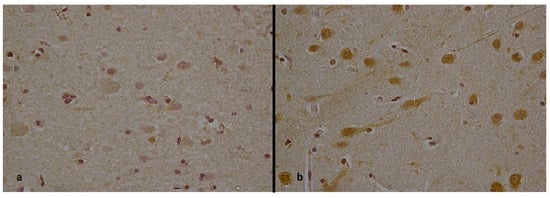

| Bazille et al. (2005) [38] | 63-year-old man | Heat-stroke-related death of a man discovered unconscious outdoors with generalized seizures. He had chronic alcoholism and schizophrenic psychosis treated with olanzapine. He died from multiorgan failure 28 h after admission. | On admission to hospital, the temperature was 43 °C. | - | - | Acute cerebellar lesions with vacuolation of the myelin sheath, which was particularly striking around the dentate nuclei. | Laboratory tests showed an elevated serum lactate, a mild elevation in plasma creatinine, and a decreased platelet count. Routine toxicologic screening was negative. Positive results from the immunohistochemical reaction for HSP-70 in the cerebellar cortex. |